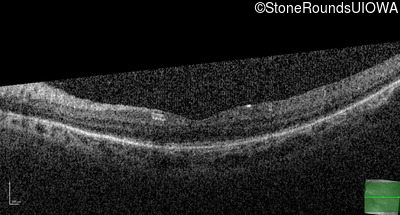

Optical Coherence Tomography - Right - 20/50 +1

Exemplar / OCT Stack